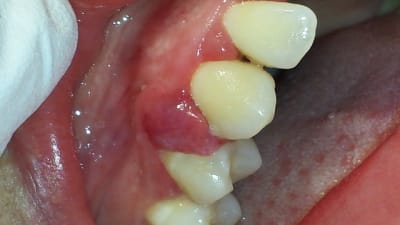

bonsoir, j'ai reçu une patiente en consultation pour "un problème de gencive qui saigne et qui est douloureuse".

a l'examen, on observe une gencive inflammatoire entre 13-14.

13+14 test de vitalité ok; poche paro entre ces 2 dents

j'ai de suite penser a un épulis inflammatoire.

un avis sur l'étiologie et la conduite a tenir?